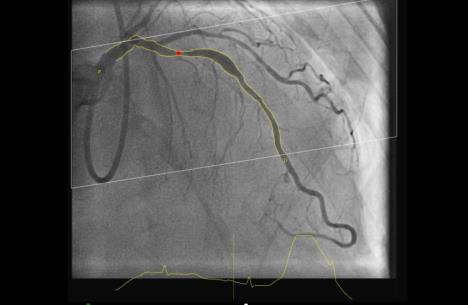

- Pomoću ovog softvera pravi se 3D rekonstrukcija snimka arterija, dobijenog koronarografijom, koja daje preciznije podatke o procentu suženja, prečniku naslaga i dužini opstrukcije krvnog suda. Ovaj savremeni program 3D rekonstrukcije slike suženog ili zacepljenog krvnog suda, zapravo, procenjuje stepen pada pritiska u njemu. Ova procedura u kojoj je softverski nalaz procenitelj težine bolesti, odnosno, stepena začepljenja krvnog suda je, zapravo, zamena invazivne metode FFR, kojom se do sada uspostavljala dijagnostička slika, ali na invazivan način uz upotrebu žica, katetera i kontrasnih sredstava - navodi se u saopštenju i dodaje:

- Virtuelna rezerva frakcionog protoka (vFFR) je fantastična zamena koja precizno i za kraće vreme, razotkriva sve pokazatelje stenoze sa ranije dobijenog koronarnog snimka, a uz pomoć računarskog modelovanja dinamike fluida. Zato, za ovakav metod možemo reći da predstavlja zlatni standard u proceni stenoze koronarnih arterija, kojim se ubrzava najpreciznije donošenje kliničkih odluka i omogućava brza procena da li suženje na krvnom sudu zahteva ugradnju stenta, ili se stenoza može lečiti i uz pomoć lekova.Đ'e8 Kada se vizuelno procenjuje stepen suženja stenoze na krvnim sudovima srca, nije uvek moguće sa sigurnošću utvrditi da li se radi o hemodinamski značajnim naslagama, ili ne.